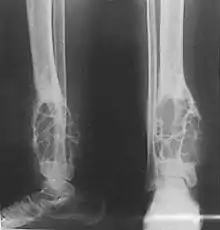

Radiografía mostrando un adamantinoma de tibia

Se presenta predominantemente en huesos con localización subcutánea como la tibia. Por lo general los pacientes están en su segunda o tercera década de vida, aunque puede ocurrir en un rango bastante amplio de edad.